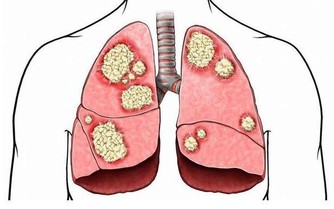

1. 肺癌:咳嗽及咳血

咳嗽是身體清除刺激肺部異物的方式,過敏或流感會讓你咳嗽,這很常見。但是,如果你持續咳嗽卻沒有其他症狀,可能需要進行篩查。尤其如果你是一個老煙民並且總咳嗽,就不要拖延下去了,吸煙時間越長,患肺癌的風險就越大。